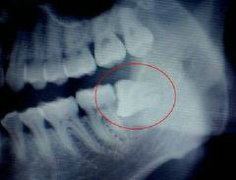

长智齿了,拔还是不拔呢?对此,专家表示,并不是所有的智齿都要拔除,但有四种智齿,非拔不可!接下来,爱齿尔为您揭开这四种智齿...